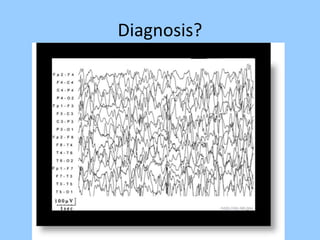

1. The document discusses EEG patterns and findings in various neurological conditions seen in children. It includes descriptions of normal EEG findings as well as abnormal patterns seen in conditions like absence seizures, West syndrome, benign childhood epilepsy with centrotemporal spikes, Lennox-Gastaut syndrome, non-convulsive status epilepticus, subacute sclerosing panencephalitis, and herpes encephalitis.

2. Case studies are presented with clinical histories and EEG findings to illustrate different pathologies. Treatment options are also mentioned for many of the conditions.